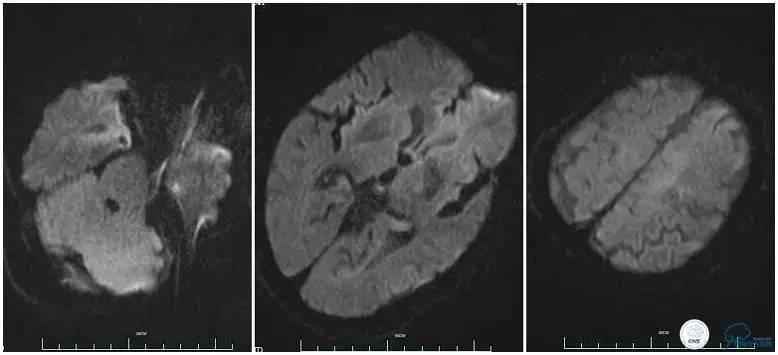

辅助检查:血常规、生化、凝血功能未见明显异常,心电图:窦性心律,ST-T改变;头颅CT平扫:未见明显出血。头颅MRI:未见新鲜梗塞灶;头颅MRA:双侧大脑前动脉远端缺如。

术前头颅MRI。

3.该患者治疗过程中存在一定不足,患者右侧肢体偏瘫症状明显,取栓过程中因血管扭曲未能优先处理左侧大脑前动脉。虽然术后血流完全再通,但复查头颅MRI左侧大脑前供血区域仍有大片梗死,右侧上肢肌力恢复不理想。